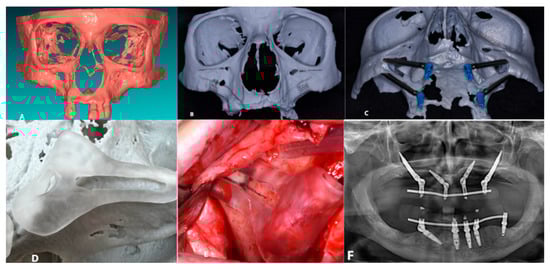

The patient experienced no immediate post-operative issues. The 6-month postoperative follow-up confirmed the stability of all implants, with no complications reported (Figure 1).

Figure 1. (A) Creation of the SLA model; (B) Pre-operative study of the patient’s anatomy; (C) Pre-operative simulation of the implant preparation surgical procedure; (D) SLA and surgical guide; (E) Bone-supported surgical guide; (F) 6-Month Follow-Up.